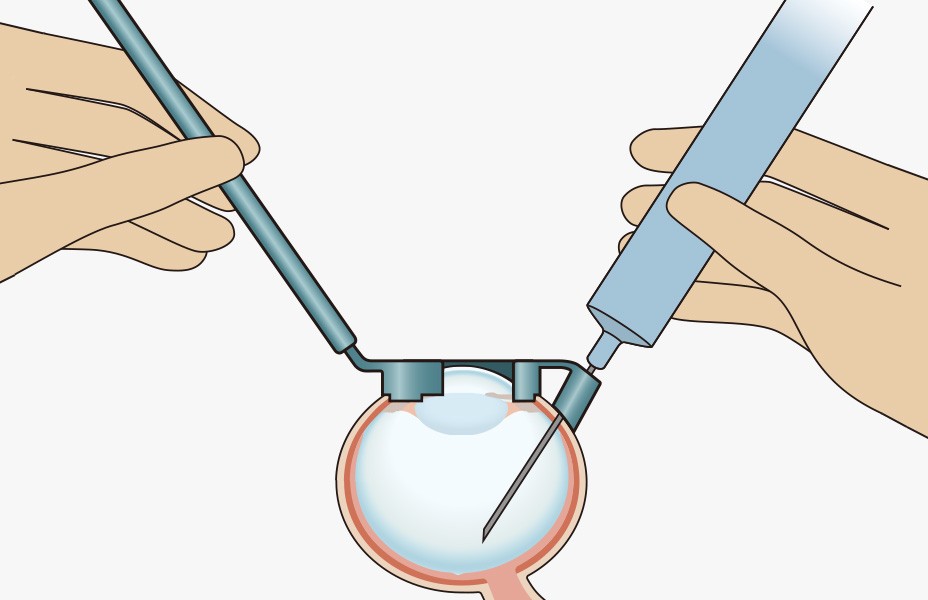

手順4:注入

■注射針の角度と深度は一定に保たれています。

■網膜や水晶体に損傷を与えることなく網膜付近に薬剤を注入することができます。

手順5:注射針抜去

■注射ガイドで強く圧迫し続けると硝子体が脱出することがあります。